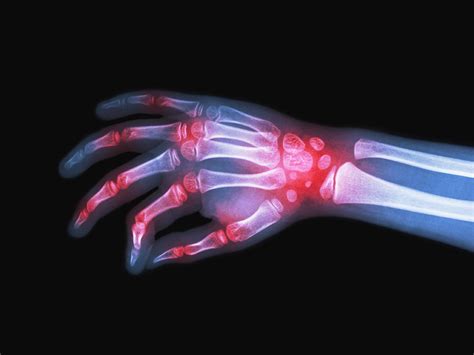

A AR geralmente se manifesta com dor, edema, calor e rigidez nas articulações afetadas. A rigidez matinal, com duração superior a 30 minutos, é uma característica distintiva da AR. As pequenas articulações das mãos e dos pés são frequentemente as primeiras a serem envolvidas, com um padrão simétrico de acometimento. Além das manifestações articulares, a AR pode causar sintomas sistêmicos, como fadiga, febre baixa, perda de apetite e perda de peso. Manifestações extra-articulares, como nódulos reumatoides, vasculite, doença pulmonar intersticial e pericardite, também podem ocorrer.

O diagnóstico da AR baseia-se em uma combinação de critérios clínicos, laboratoriais e radiológicos. Os critérios de classificação da AR do American College of Rheumatology (ACR) / European League Against Rheumatism (EULAR) 2010 são amplamente utilizados para fins de diagnóstico e pesquisa. Os exames laboratoriais relevantes incluem a pesquisa do fator reumatoide (FR) e dos anticorpos anti-peptídeo citrulinado cíclico (anti-CCP). Os exames de imagem, como radiografias, ultrassonografia e ressonância magnética, podem auxiliar na avaliação da extensão do dano articular.